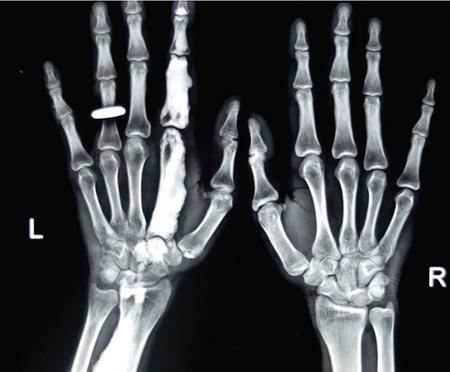

MISCELLANEOUS PAEDIATRIC RADIOGRAPHY – TECHNIQUES AND INTERPRETATION: SKELETAL SURVEY Padma V. Badhe The skeletal survey, generally performed in children, is a set of radiographs done in order to evaluate the entire skeleton. A skeletal survey, commonly used to evaluate skeletal dysplasias, acquired metabolic disorders and suspected child abuse, is still the key radiological investigation for the same. Hence, an explicit understanding of the technique along with the common disorders forms the basis of making a diagnosis in these paediatric pathologies. A skeletal survey is done for various skeletal dysplasias, non-accidental injury (battered baby syndrome) and suspected child abuse. It can also be done in cases of metabolic bone diseases, disseminated infections, multiple myeloma, eosinophilic granuloma. It is also used in evaluation of metastatic bone diseases and polyarticular arthropathy. Orthogonal views of the skull, spine, pelvis and one extremity are taken, preferable in standing position. For preterm babies/newborns, AP and lateral views of babygram may be taken. Projections: For skeletal dysplasias: Additional views: Both extremities may be taken if epiphyseal abnormalities and limb asymmetry is present. Focused views for specific pathologies may be taken. When a diagnosis remains uncertain, 1 year follow up is usually recommended. For preterm babies/newborns: AP and lateral views of babygram may be taken with additional specific views for extremities. For suspected non-accidental injury (NAI): AP and oblique view of chest is taken for better evaluation of the ribs. AP view of abdomen with pelvis. Both upper and lower limbs are evaluated. In lower limbs, two projections in AP and lateral (one with both femur including hip and knee joints; and another for foot and ankle) is taken. AP and lateral views of whole spine, skull. Oblique view of hands. A babygram should be avoided in cases of NAI, as subtle fractures are easily missed. Proper legal documentation while taking the views is very important and ideally two health care professionals must be present. For metabolic disorders: entire skeletal survey is usually not required. Specific views of hands, knees and spine may be taken with additional views depending on the suspected pathology. Centring point: Varies according to the part being examined. Angulation, collimation and orientation: Varies according to the part being examined. Images must be well collimated to obtain lower radiation dose. Detector size: Varies according to the part being examined: 8″ × 10″, 10″ × 12″, 11″ × 14″. Exposure: Ideally high kVp images are taken to reduce radiation dose. But in suspected NAI, low kVp/high mA images are recommended to better demonstrate findings. SID (Source Image Distance):100 cm Grid: Grids are not routinely used to image spine, pelvis, skull and abdomen in children. Radiation dosage: 0.3–3 mSv Essential image characteristics: Adequate spatial resolution, high signal to noise ratio, low kVp (50–70) for high contrast should be done. Excellent bone and soft tissue details are required. The presentation of skeletal dysplasia can range anywhere from minimal stunting of growth and bowing of limbs to severe dwarfism and multiple fractures. Knowledge of the commonly encountered dysplasias with an approach to arrive at a diagnosis is vital in any Radiologist’s practice The following flow chart summarizes the classification of important skeletal dysplasia: The following table summarizes the various dysplasias affecting the axial skeleton: TABLE 7.5.1.1 The following flow chart summarizes the working approach to skeletal dysplasias: Osteopetrosis (Albers-Schonberg disease/Marble bone disease) (Fig 7.5.1.1): Osteopetrosis clinically presents with anaemia/thrombocytopenia or cranial nerve compression. Radiological features include generalized increase in bone density with loss of medullary space. However, cortico-medullary appreciation with cortical thinning is also rarely seen. Bone within bone appearance with Erlenmeyer flask deformity is also noted. Pyknodysostosis (Figs. 7.5.1.2 and 7.5.1.3): patient presents with short stature. Unlike osteopetrosis, there is no anaemia. Radiographs show generalized increase in bone density with preserved medullary canal. There is mandibular hypoplasia with obtuse angle. Acro-osteolysis is also a feature. Dental caries with osteomyelitis of the jaw may be seen. Sclerosing dysplasia presenting as wavy undulating new bone formation. Usually monomelic, lower limb and along one side. The classic appearance is described as Dripping candle Wax sign. It is a Sclerosing dysplasia with radiological features of symmetric juxta-articular involvement in epimetaphyseal region. They are 1–10 mm in diameter and uniform in size. No metabolic activity is seen on bone scans. This skeletal dysplasia shows diffuse decrease in bone density with paper-thin cortex. Fractures heal in normal time but shows callus with poorly cellular matrix. Wormian bones and enlarged sinuses may be seen. Codfish vertebra (Biconcave vertebra) may be seen. Metaphyseal corner fractures are not seen in osteogenesis imperfecta that helps to differentiate it from battered baby syndrome. There are four types of OI out of which type one is most common (Figs. 7.5.1.6 and 7.5.1.7). The radiological features of MPS include Osteopenia and Universal platyspondyly. The intervertebral disc spaces are maintained. Proximal pointed metacarpals is an important radiological finding. Hurler’s syndrome show anteroinferior beaking with short and wide metacarpals. Varus deformity of humerus is characteristically seen in Hurler’s syndrome (Fig. 7.5.1.8). Mental retardation & corneal clouding is seen in Hurler’s syndrome whereas these Hunter’s disease has normal intelligence with no corneal clouding. Morquio’s syndrome shows central beaking (Fig 7.5.1.9). This skeletal dysplasia shows normal bone density with rhizomelic limb shortening and normal trunk. Narrowing of spinal canal is classically seen with decrease in the Interpedicular distance caudally. Other radiological features include trident hand (separation of middle & third fingers), Champagne glass pelvis (short, flat ilia and small sciatic notch), bullet nose vertebra and overexpansion of skull with narrow foramen magnum (Fig. 7.5.1.10). This skeletal dysplasia is characterized by normal bone density with dwarfism and normal craniofacial skeleton. The interpedicular distance is normal. There is severe platyspondyly with anterior tonguing (disappears at older age). Other radiological features include increased disc space, short stubby metacarpals, small irregular epiphysis and widened metaphysis. Anterior tonguing is a feature of Pseudoachondroplasia. This form of skeletal dysplasia involves the spine and epiphyses (Fig. 7.5.1.11). There is normal bone density with rhizomelia. Spine and Pelvis can be involved. Premature osteoarthritis can be seen. The other characteristic features include Platyspondyly and small irregular epiphysis. There are two forms Spondyloepiphyseal dysplasia Congenital and Spondyloepiphyseal dysplasia Tarda. Spondyloepiphyseal dysplasia Congenita is Autosomal dominant and shows pear-shaped vertebrae. Spondyloepiphyseal dysplasia Tarda is X Linked recessive with heaped up vertebrae. It has two forms. The first form is Conradi Hunermann syndrome which is autosomal dominant characterized by asymmetric limb shortening with metaphyseal flaring (Fig. 7.5.1.12). The Autosomal recessive form is Fatal in first few years. Rickets: Rickets refers to deficient mineralization of the growth plate in the paediatric population due to deficiency of vitamin D. In an immature skeleton, there is abnormal mineralization at the zone of provisional calcification in the metaphysis due to osteoid deposition resulting in widening of the growth plate. The features of rickets include fraying, splaying and cupping (Fig. 7.5.1.13). Fraying denotes indistinct margins of the metaphysis whereas splaying denotes widening of metaphyseal ends. Term ‘Cupping’ is used for increased concavity of the metaphysis. These findings are typically seen involving areas of active growth (e.g. distal femur and proximal tibia in the knee) Bowing is a result of associated osteomalacia leading to weakening of weight-bearing lower limb bones. Other bone deformities such as genu valga, genu varum, protrusio acetabuli can also be seen. The lower ribs may also be drawn inwards inferiorly by the attachment of the diaphragm this is called Harrison’s sulcus. Scurvy: Scurvy is a result of dietary deficiency of Vitamin C (ascorbic acid). The classic presentation is that of a patient with an increased bleeding tendency and osteopenia with poor wound healing. Features of scurvy include generalized osteopenia with cortical thinning termed as ‘pencil-point’ cortex. Other radiological findings include the periosteal reaction due to subperiosteal haemorrhage. Expansion of the costochondral junctions occurs forming scorbutic rosary. Bleeding into the joint spaces may result in hemarthrosis. Circular, opaque radiologic shadow surrounding epiphyseal centres of ossification may result from bleeding (Wimberger ring sign) (Fig. 7.5.1.14). Frankel line may be seen. It represents dense zone of provisional calcification. Lucent metaphyseal band is seen underlying Frankel line called as Trümmerfeld zone. Metaphyseal spurs may be seen that result in cupping of the metaphysis (Pelkin spur). Pelkin fracture (metaphyseal corner fracture) can also be seen. Images obtained must be of good resolution with adequate bone and soft tissue details. Additional views: They have already been described in positioning. CT Brain in can be done in cases of NAI to look for subdural hematomas. A skeletal survey is the first-line imaging modality for evaluation of skeletal dysplasia, nonaccidental injury and metabolic bone diseases. The skeletal survey must be tailored according to the respective indication. It helps to characterize syndromic patterns in skeletal dysplasias, with evaluation of complications. In cases of diagnostic dilemmas, additional focused view and occasionally yearly follow-up is recommended. A high index of suspicion is needed in utilizing skeletal survey as a diagnostic modality in NAI. At the same time, one must also remember the legal and social implications of making this diagnosis. BABYGRAM Babygram is a colloquial term used for a radiograph of the whole body of a newborn or just the chest and abdomen (thoracoabdominal babygram) on a single image. As the name suggests it is a rather non-targeted study. It is most commonly requested after line placement. Evaluation of skeletal abnormalities in a deceased foetus is typically performed using anteroposterior and lateral views of a babygram. It helps in pointing out skeletal causes of death in stillborn or dead foetuses. This will help the treating physician and parents understand the reason for baby’s death. This will also help in future genetic counselling of the couple. Sometimes chest or abdominal radiographs of the baby are requested but due to radiographers error or inexperience with small babies, there is inclusion of the region not to be assessed leading to a false babygram. Babygram is most frequently done after line placement in neonates, to view the position of the umbilical vein or artery catheter and to confirm appropriate placement. It is a useful modality in skeletal dysplasias (Fig. 7.5.1.15) like osteogenesis imperfecta, thanatophoric dysplasia and chondrodysplasia punctata. It can also be used for skeletal deformations probably caused by foetus akinesia and in cases of Caudal regression syndrome. In stillborn foetuses, it is used for evaluation of skeletal dysplasias prior to an autopsy (Fig. 7.5.1.16). It is also used in screening for surfactant deficiency and in cases of Necrotizing Enterocolitis in preterm babies where it can help to see the bowel dilatation, intramural and portal venous gas. It can be done in aneuploidies like trisomy 18 and in cases of sudden infantile death syndrome. All the essential equipment and room need to be prepared including the exposure factor. This should be done prior to placing the baby on the table to prevent any neonatal heat loss. Ensure that the baby is correctly identified. Give brief explanation to the patient’s parents regarding the procedure, its risks and benefits. Ensure that the accompanying relative is not pregnant (if female). Parents/guardians/nurses should be instructed to hold the baby with arms above the head and legs straight down. Sandbags/tapes can be used to immobilize the baby. Avoid taking the radiograph when baby is crying. Normal appearance: The endotracheal tube should lie in the lower third of trachea, distance can vary with position of baby’s head. Umbilical artery catheter has an inferior dip along the internal iliac artery, which then turns superiorly along the aorta. The tip should lie in the mid-thoracic aorta (T6–T10) or lower (L3–L4) away from aortic branches to prevent any thrombosis. Umbilical venous catheter does not have the inferior curvature, but rather a posterolateral angulation to the right near the liver through the ductus venosus. The tip should lie in the superior IVC or right atrium at T8/T9 vertebral level (Fig. 7.5.1.17). Portal venous gas may be seen initially after insertion. In a stillborn foetus, the approximate gestation age of the foetus and corresponding ossification centres must be known. In early gestation, the lack of appearance of an ossification centre may be mistaken for skeletal dysplasia. Both chest and abdomen should be included. In a rotated patient, the distance between the spinous process to medial end of clavicles will be asymmetric. The medial end of clavicle should overlap the lung apex, if above, suggests lordotic image. Motion artefacts to be reduced as much as possible. A crying neonate may result in an expiratory film, and hence must be evaluated accordingly. In evaluation of skeletal dysplasias in the newborn, additional views of skull and hand have to be obtained. Baby gram is a useful diagnostic investigation for position of the paediatric umbilical catheters. It helps in general survey in skeletal dysplasia (Fig. 7.5.1.18). It is a simple, effective study in deceased foetus for diagnosis and further counselling, sometimes obviating the need for an autopsy. As baby gram is a non-targeted study, it increases the dose of radiation for the baby. As the exposure settings remain same for the entire body of the baby, the quality of the image decreases. This increases the chances of missing subtle findings. The babygram in a neonate is currently used to localize umbilical catheters. In stillborn fetuses, it is still an important study for documenting and confirming skeletal dysplasias. Understanding the normal appearance as per gestation age and patterns of various common skeletal dysplasias is essential for evaluation. Being a non-targeted study, it should not be used as an alternative study to evaluate the chest or abdomen considering radiation exposure and poorer image quality. INVERTOGRAM Invertogram was first described by Wangensteen and Rice in 1930. It was used as a first investigation to be ordered in evaluation of infants with clinically diagnosed or suspected Anorectal Malformation (ARM). ARM is a serious but surgically treatable congenital malformation with approximate incidence of 1 in 5000 live births. Though the diagnosis of this condition is based on clinical history and physical examination, imaging plays an important role in deciding the type of ARM, and associated complications to aid in management. International classification of anorectal malformations is as follows. Syndromic association is seen as a part of VACTERL defects, trisomy 21 13 and 18, Klippel Feil syndrome, cat eye syndrome etc. The main indication of Invertogram is to evaluate anorectal malformation in a neonate. A radio-opaque marker is placed over the external anal opening. Infant is held inverted by holding both thighs, maintaining this posture for at least 5 minutes before taking an X-ray in true lateral position (Fig. 7.5.1.19). Exposure is made during inspiration. The Invertogram should ideally be done 24 hours after birth as, the rectal gas may not reach the terminal segment if study is done too early. Pubo-coccygeal line (PCL) is drawn from upper border of pubic symphysis (which corresponds to centre of pubic bone on lateral X-ray) to sacrococcygeal junction. I point is the inferior most point of ischial ossification centre. A line which is drawn parallel to PC line passing through the I point is called I line. ‘A’ point is represented by marker placed at anal pit. The position of rectal pouch gas shadow is observed with respect to these lines and appropriate diagnosis is made (Fig. 7.5.1.21). A diagnosis of high ARM is made when gas shadow of rectal pouch is cranial to PCL. If rectal pouch gas shadow is in between PCL and I line, it is called as intermediate ARM and if it is caudal to I line, it is diagnosed as low ARM. Gas in urinary bladder or vagina or beaking of gas shadow of rectal pouch indicates fistula into one of these sites. Associated congenital abnormalities like spinal defects are also looked for in the invertogram (Fig. 7.5.1.22). Invertogram done too early (less than 24 hours) may not demonstrate rectal gas. Meconium plugging the terminal segment gives false position of the rectal gas. Positioning can cause discomfort to child and an irritated crying child actively contracts the sphincter muscles, pushing the gas shadow higher. Rectum may be pulled cephalad due to gravity in inverted position. The rectal gas may escape through an associated fistula. Erroneous interpretation can also occur due to sacral anomalies and when gas in vaginal cavity is misinterpreted as distal rectal gas. Both ischial bones should superimpose and terminal blind loop should be well distended. It is an easily available modality and can be done quickly, does not require additional equipment. It has lesser radiation dose as compared to CT invertogram. It provides a rough guide as to the type of ARM and decides management. Higher localization of obstruction due to various causes like meconium plugging, imaging done too early etc. as described above in pitfalls. It is more uncomfortable to the baby as compared to the prone cross-table lateral view, and a crying baby contracts the puborectalis leading to erroneous results. K. L. Narasimharao et al. modified the technique and proposed cross-table lateral view for evaluation of infants with ARM’s which has shown equal or better information and has now replaced invertogram (Fig. 7.5.1.23). Prone cross-table lateral view is considered equivalent or even better in determining the level of anomaly. Positioning is in this view is prone in genupectoral position (at least for 3 minutes). It is taken in true lateral and during inspiration. The lines used to delineate types of ARM is essentially the same as in an invertogram. It is preferred over invertogram as relatively easy positioning of the infant and less discomfort allows for better cooperation of neonate during the study. It also eliminates the effect of gravity. ARM with fistula is better delineated as, in an invertogram, fistula/gas is at the highest level and gas may escape through it. CT invertogram is another modality that delineates anatomy better but is rarely used. In the era of cross-section imaging, MRI and USG have opened new modalities for accurate diagnosis of ARM, but invertogram being readily available, inexpensive, quick and cost-effective is used as first investigation for evaluating a patient with suspected or confirmed case of ARM. Cross-table lateral view has replaced invertograms as it is more patient-friendly and equally effective. UPPER GASTROINTESTINAL SERIES Rushit S. Shah An upper gastrointestinal (GI) study is a radiographic examination of the GI tract from the pharynx to the ligament of Treitz after oral administration of contrast agent. The use of upper GI studies is gradually declining with the increasing availability of paediatric endoscopy and the challenge for the modern radiologist to work in conjunction with the surgeon and gastroenterologist to select the right patients for an upper GI series. However, the upper GI series remains the key for demonstrating many anatomical abnormalities. The upper GI series is also useful in evaluating gastro-oesophageal reflux in conjunction with 24 pH monitoring. The upper GI examination is useful in evaluating many conditions including but not limited to: